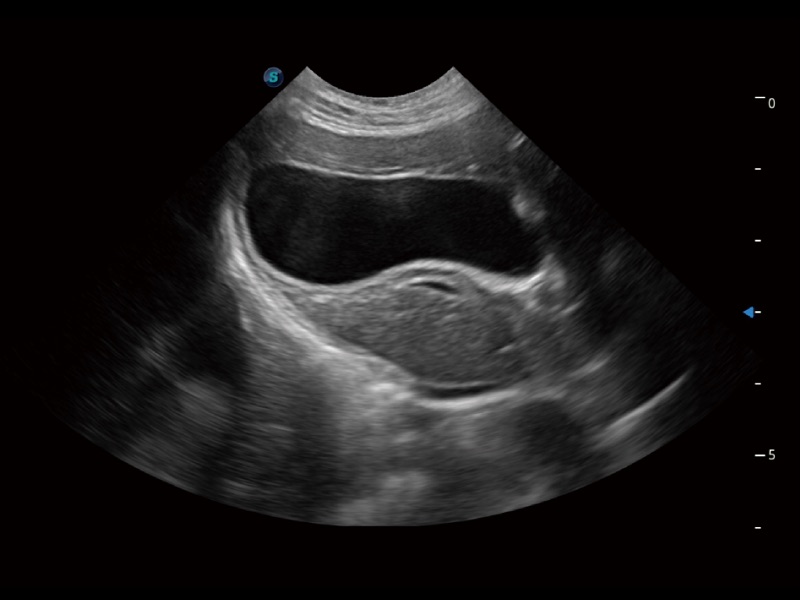

(猫)胆囊

(猫)肺动脉血流频谱